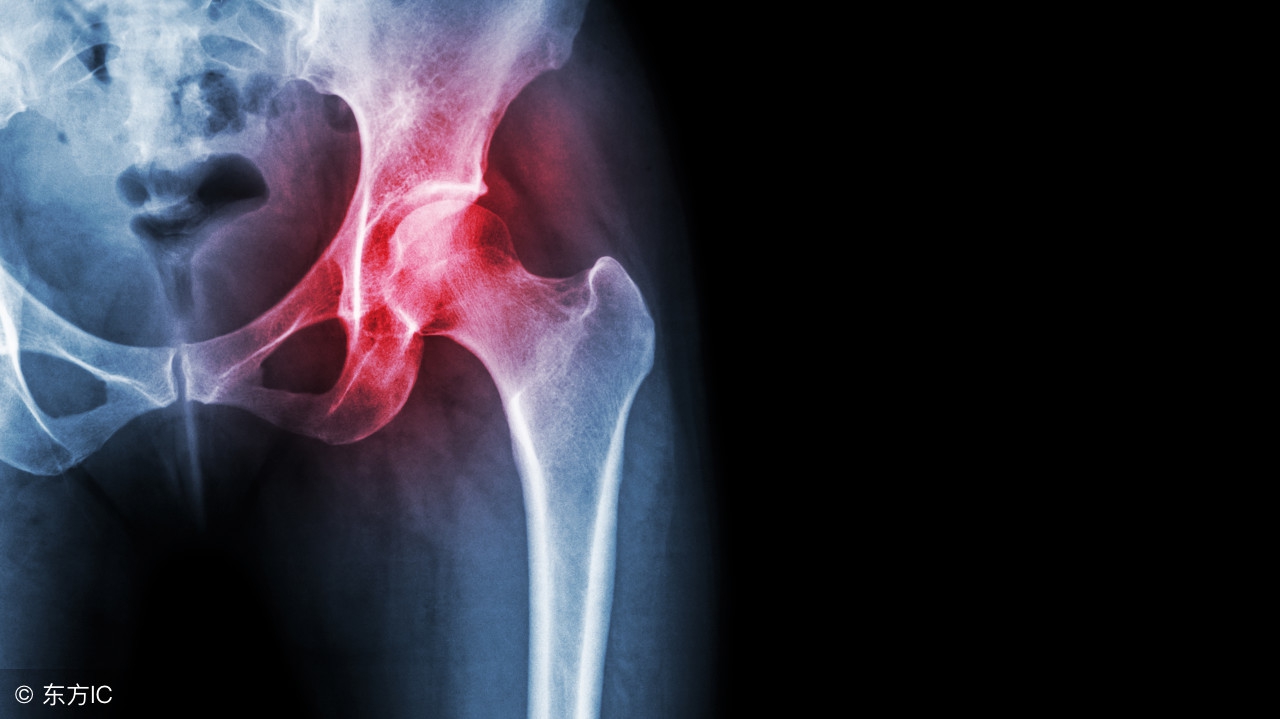

股骨头——位于人体髋关节内,就像一个门轴,在人体站立时几乎承受着人体全身负重。

股骨头坏死——由各种原因导致的股骨头局部血运不良,逐步引起骨细胞缺失、坏死、骨小梁断裂、股骨头塌陷的一种病变。

股骨头一旦出现坏死,八成患者会在1-4年内出现塌陷;一旦发生塌陷,九成患者会在2年内丧失独立行走和生活自理能力,变成残疾!